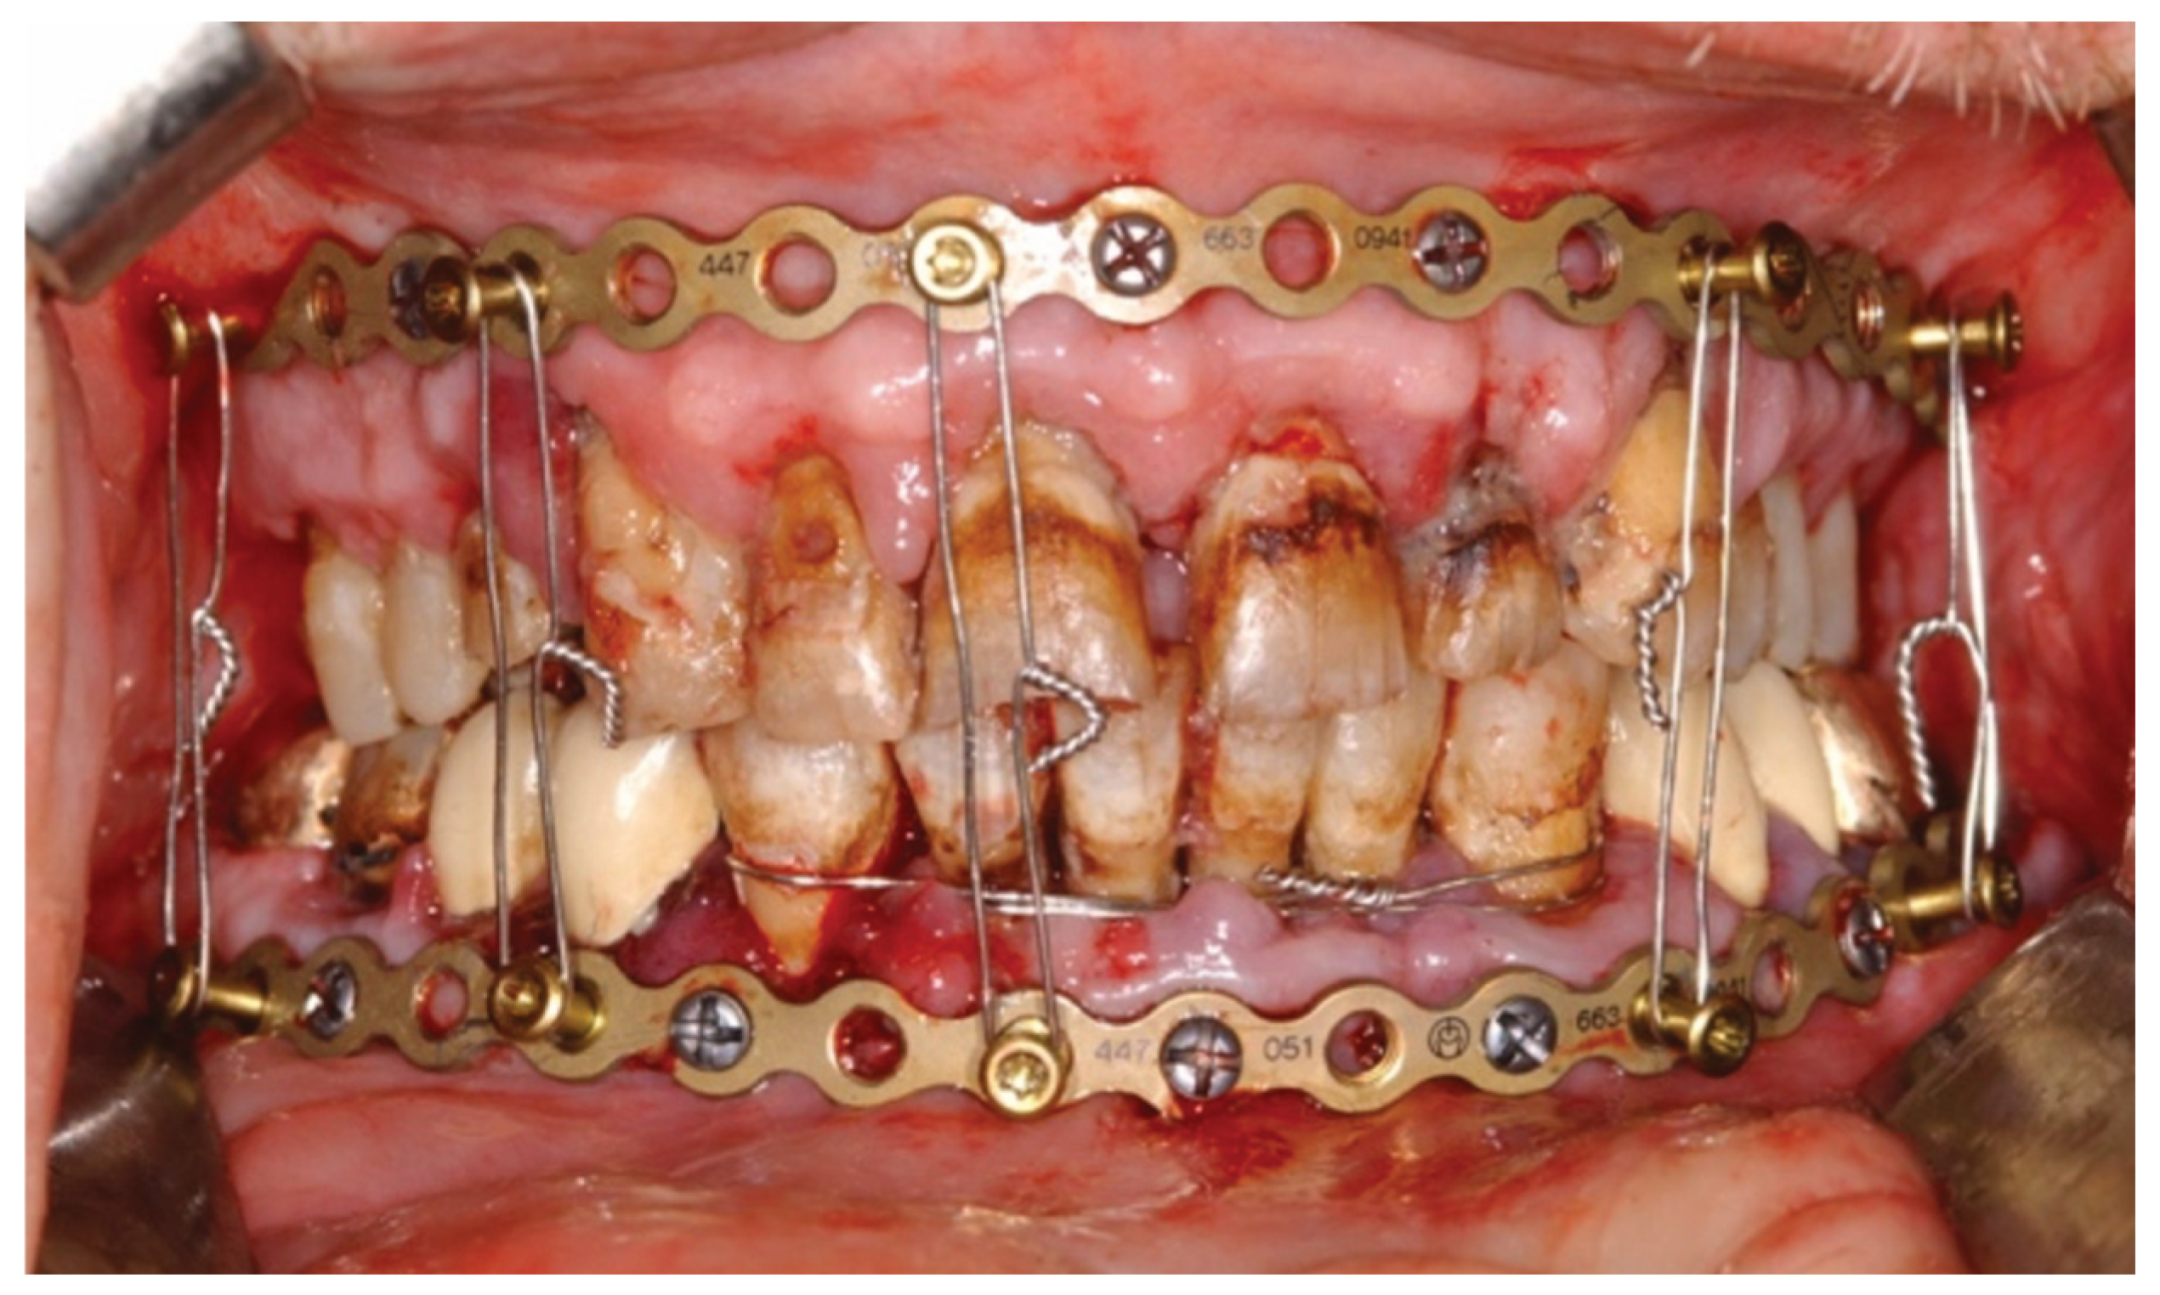

3.3. ‘In-Situ-Bending’ for Fracture Reduction